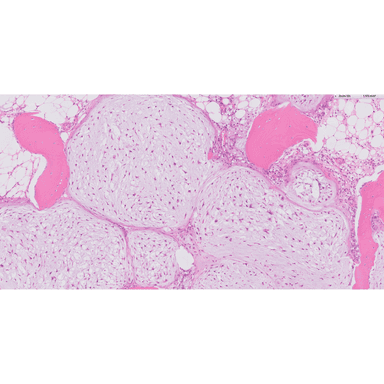

Schistosomiasis

Pleomorphic liposarcoma